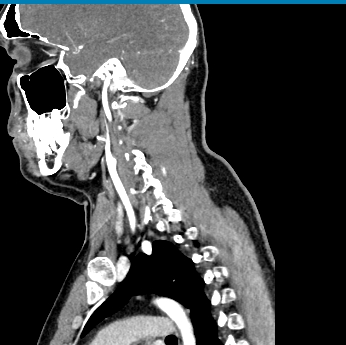

Мультиспиральная КТ сосудов шеи (КТ-ангиография) включает в себя сканирование брахиоцефальных артерий, то есть как сосудов кровоснабжающих головной мозг, так и проксимальные отделы плечевых артерий. Это крупные сосуды, которые отходят от дуги аорты и, разветвляясь, уходят в полость черепа. К ним относятся: брахиоцефальный ствол, общие, наружные и внутренние сонные артерии, подключичные и позвоночные артерии.

КТ сосудов шеи является высокоинформативным методом диагностики патологии брахиоцефальных артерий, который позволяет выявлять участки сужения, патологической извитости, определять развитие атеросклеротических бляшек ещё до того, как появились симптомы заболевания.

В наших медицинских центрах диагностика патологии магистральных сосудов шеи проводится на современных мультиспиральных компьютерных томографах экспертного уровня TOSHIBA AQUILION. Компьютерная томография относится к лучевым методам исследования, то есть для получения изображения внутренних органов используется рентгеновское излучение. Трубка томографа при помощи рентгеновских лучей послойно сканирует область исследования с минимальной толщиной среза от 0,5 мм, затем полученные данные трансформируются в объемные изображения. Оснащение аппаратов позволяет получать снимки и трехмерные реконструкции сосудистой системы превосходного качества, при этом пациент получает минимальную дозу облучения.

Для улучшения визуализации сосудистой системы обязательным является проведение контрастного усиления. Для этого пациенту внутривенно вводится йодсодержащий контрастный препарат, который активно поглощает рентгеновские лучи и обеспечивает яркую видимость даже мелких сосудов на фоне окружающих тканей.